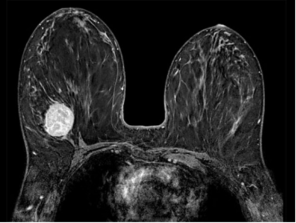

PULSE BREAST CLINIC

provides the region’s

most advanced breast care for women

including routine exams, screening and diagnostic mammograms for the detection of breast cancer, and education about general breast care.

The clinical examination ,breast ultrasound ,mammogram and biopsies are all done in the single visit as far as possible.

Diagnostic facilities offered with state of the art technology and the very best in the world.